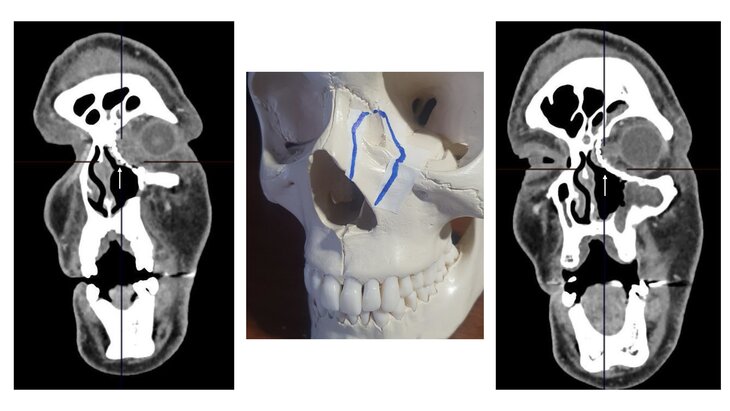

Фото: департамент здравоохранения Москвы

Команде ведущих медэкспертов из учреждений столичного департамента здравоохранения на базе ГКОБ № 1 было необходимо радикально удалить опухоль, восстановить удаленные анатомические структуры мягких тканей лица и лицевого скелета и, при этом, обеспечить физиологический отток слезы.

"Опухоль была удалена в блоке с кожей и мягкими тканями внутреннего угла век левого глаза, фрагментами носовой кости, внутренней стенки глазницы и передней стенки верхне-челюстной пазухи вместе со слезным мешком и слезным каналом. Целостность глазного яблока и глазодвигательного аппарата полностью сохранена", – рассказал завотделением хирургии опухолей головы и шеи, хирург ГКОБ № 1 Сергей Кравцов.

Кроме того, покровные ткани лица были восстановлены при помощи кожно-апоневротического лоскута со лба, добавил врач. Для сохранения бинокулярного зрения и внешнего облика лица врачи решили восстановить лицевой скелет при помощи титанового протеза. Сейчас пациент чувствует себя хорошо и доволен результатом операции.